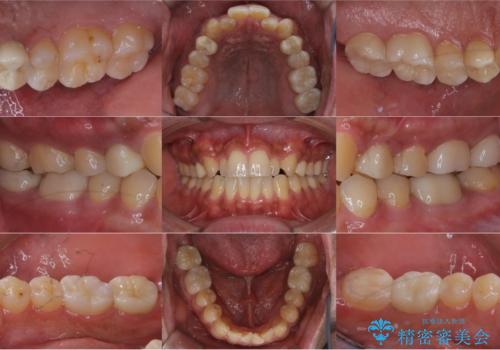

- お口の中にある銀歯を無くしたいとご相談にいらした方です。

適合の良いセラミックにてやり替えを行いました。

元々噛む力が強く、日常的に歯ぎしりもされるとの事でしたので、歯が割れてしまうリスクを軽減させるため、歯全体を覆うクラウンをメインに補綴治療を行いました。

矯正治療もご提案しましたが、ご希望されなかったため、今回は被せ物のやり替えのみ行っております。